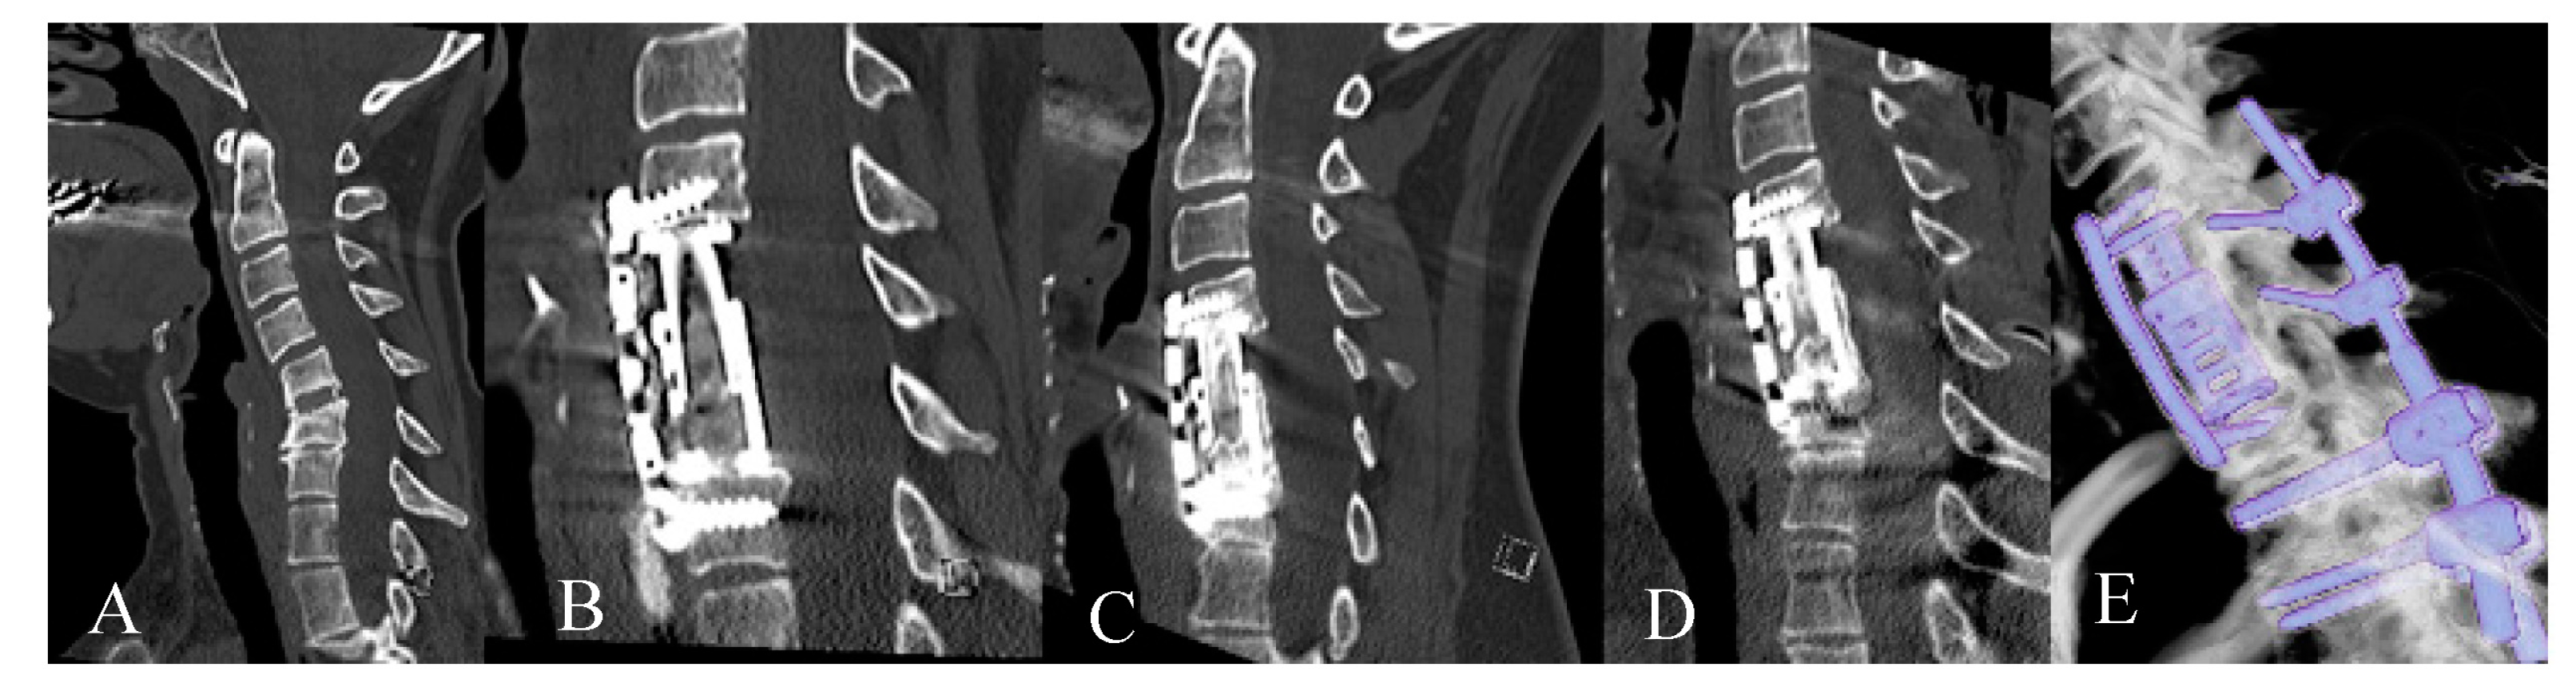

3.2. Radiological Outcome

3.3. Complications